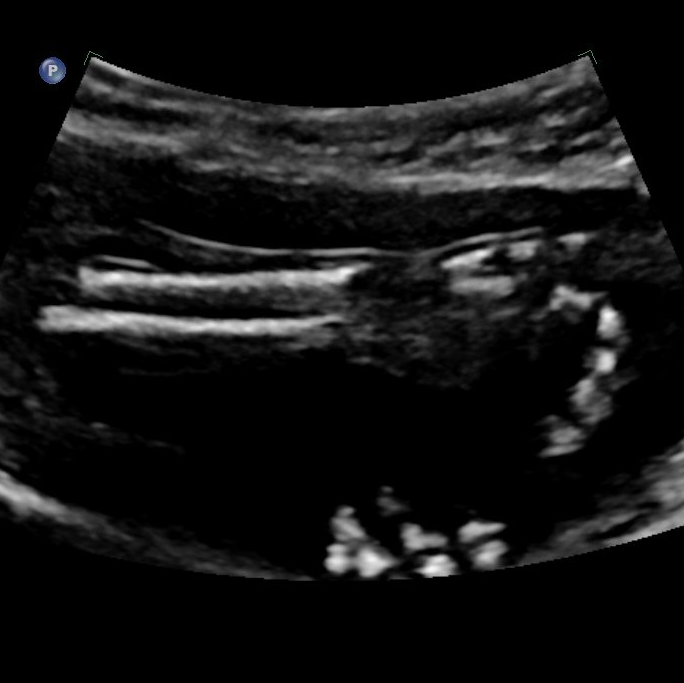

Bildtitel

Unteram mit Speiche und Elle sowie Hand